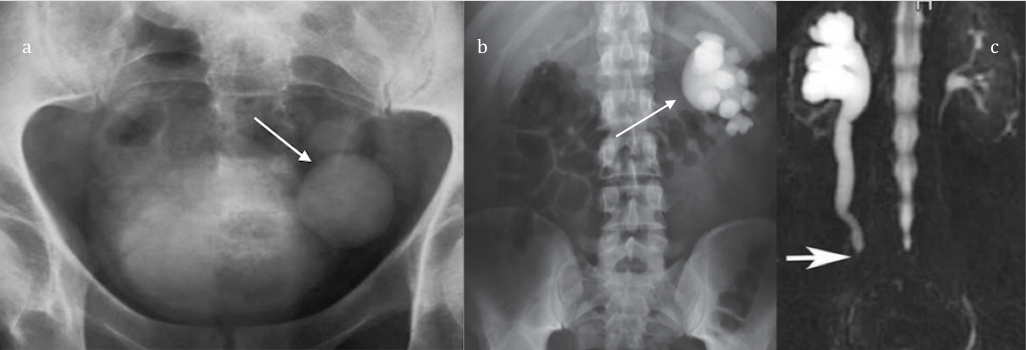

| Tres ejemplos de ectasia o estenosis de vía urinaria. a) divertículo vesical, b) síndrome de al union pielo ureteral y c) obstrucción por tumor. |